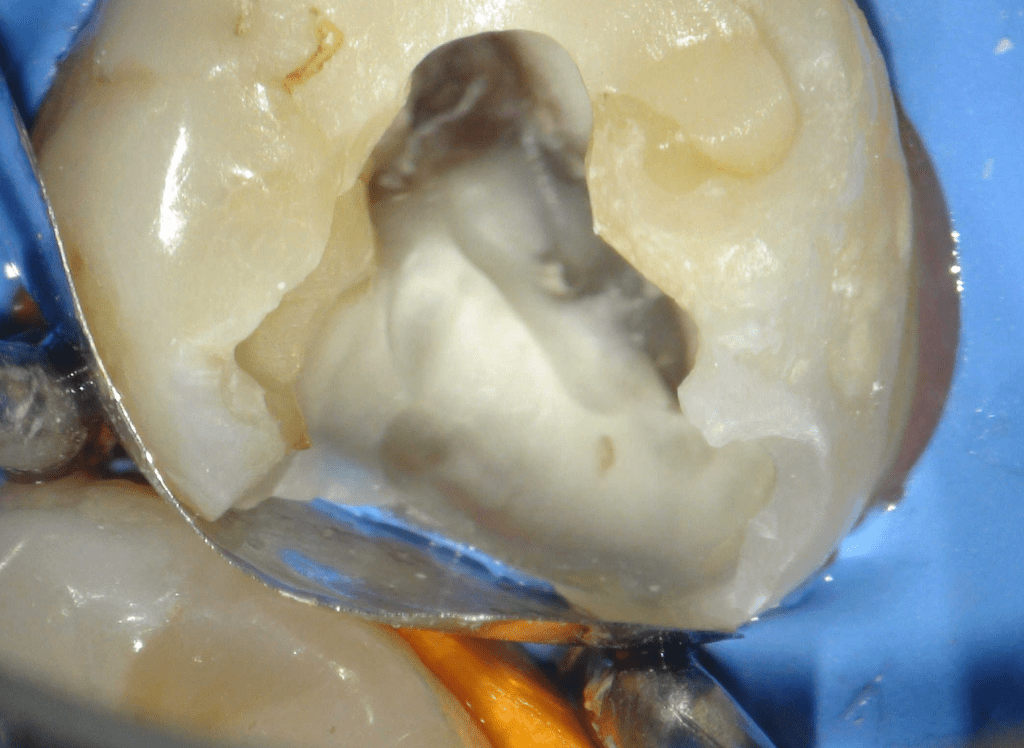

Reco preendo + 4 conductos molar superior